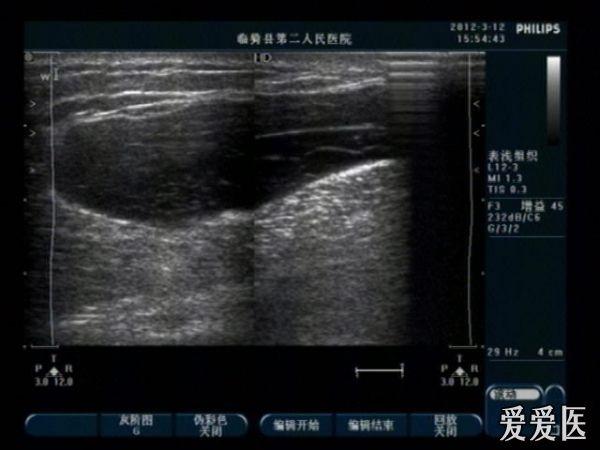

患者女,43岁,一周前做乳腺癌大扫除(腋窝淋巴扫荡“后发现腋肿大B超见:腋窝前皮下可见片状暗区回声。结合临床提示淋巴液滞留。)